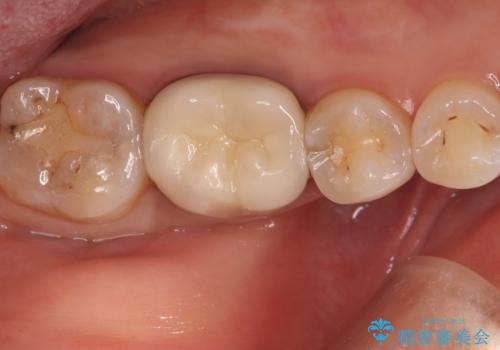

クリーニングにいらした患者さんで、右下7番目の歯の奥側の面や手前の歯との間にう蝕があり、噛む面にも蝕処置によるレジン材料が詰まっていたことから、う蝕も古い材料も全て除去しセラミックインレーでのやり替えとなりました。

右下7近遠心にカリエスを認め、咬合面のCR修復も劣化していたので、カリエスと古い材料を全て除去し新しくCR裏層した後、セラミックインレーをセットしています。セット時はラバーダム防湿を行っています。